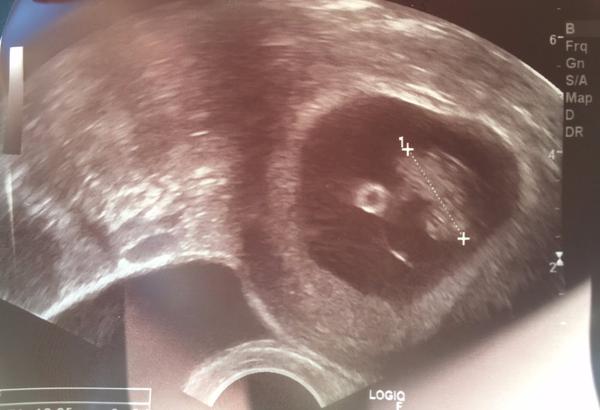

zdravím holky, včera UZ kontrola, sliznice prý krásná cca 9,4 mm. Koncem příštího týdne bude OPU dárkyně, tak se modlím aby bylo dost kvalitních vajíček.